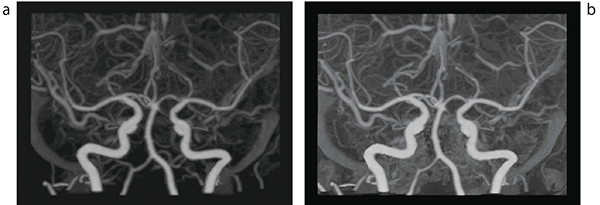

更新前のVirtualPlaceのサブトラクション機能は,造影画像から非造影画像を差分する際に,血管も含めた画像全体で差分してしまうために血管のCT値が低下する傾向があった。更新により,現在のワークステーション(WS)では一般的になりつつある,脳実質を差分対象から外して抽出する“骨以外抽出モード”が追加され,サブトラクションによる血管のCT値低下がなくなり,末梢血管の描出能が向上している(図2)。

図2 頭部CTAサブトラクション

a:従来法。全体的に血管のCT値低下が認められる。

b:骨以外抽出モード。CT値の低下がなく,末梢血管の描出能が向上している。